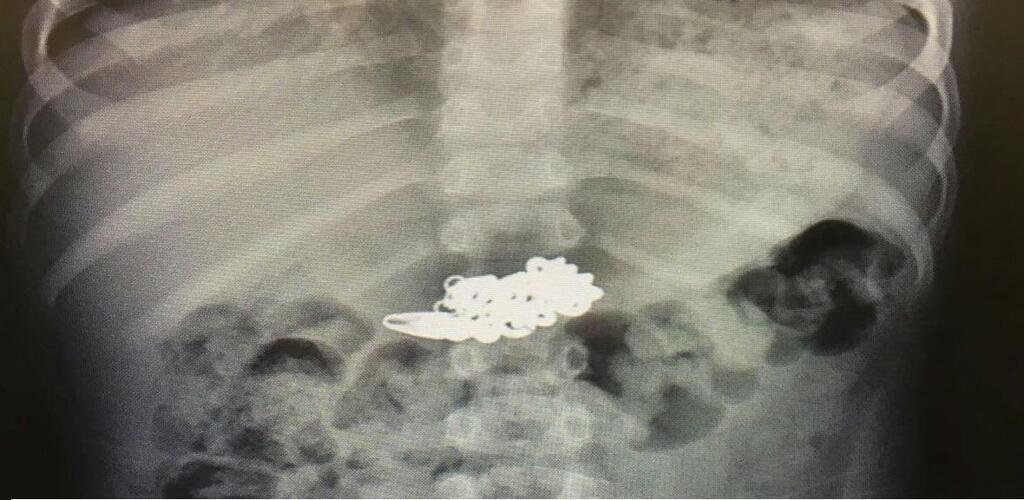

Цепочка на рентгеновском снимке. Фото: пресс-служба "Рамбам"

Снимок показал, что в желудке находился цепочка длиной 10 см. Врачи решили, что ждать ее выхода больше нельзя. Ребенка перевезли в операционную гастроэнтерологического отделения детской больницы "Рут" при "Рамбаме", сделали седацию (на иврите "тиштуш") и с помощью щадящего инструментария извлекли цепочку.